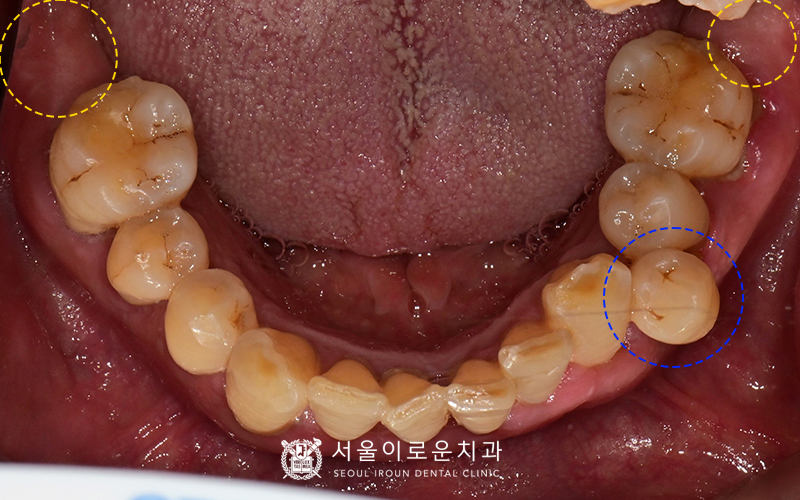

여러 각도에서 촬영한 구내사진입니다.

임상검사결과,

왼쪽 위 큰어금니와 아래 작은어금니 2개 모두

씹을 때 통증을 느끼시고

치아가 많이 흔들렸습니다.

환.자분의 경우, 치주염이 상당수 진행되어

잇몸이 많이 붓고 내려간 상태셨는데요.